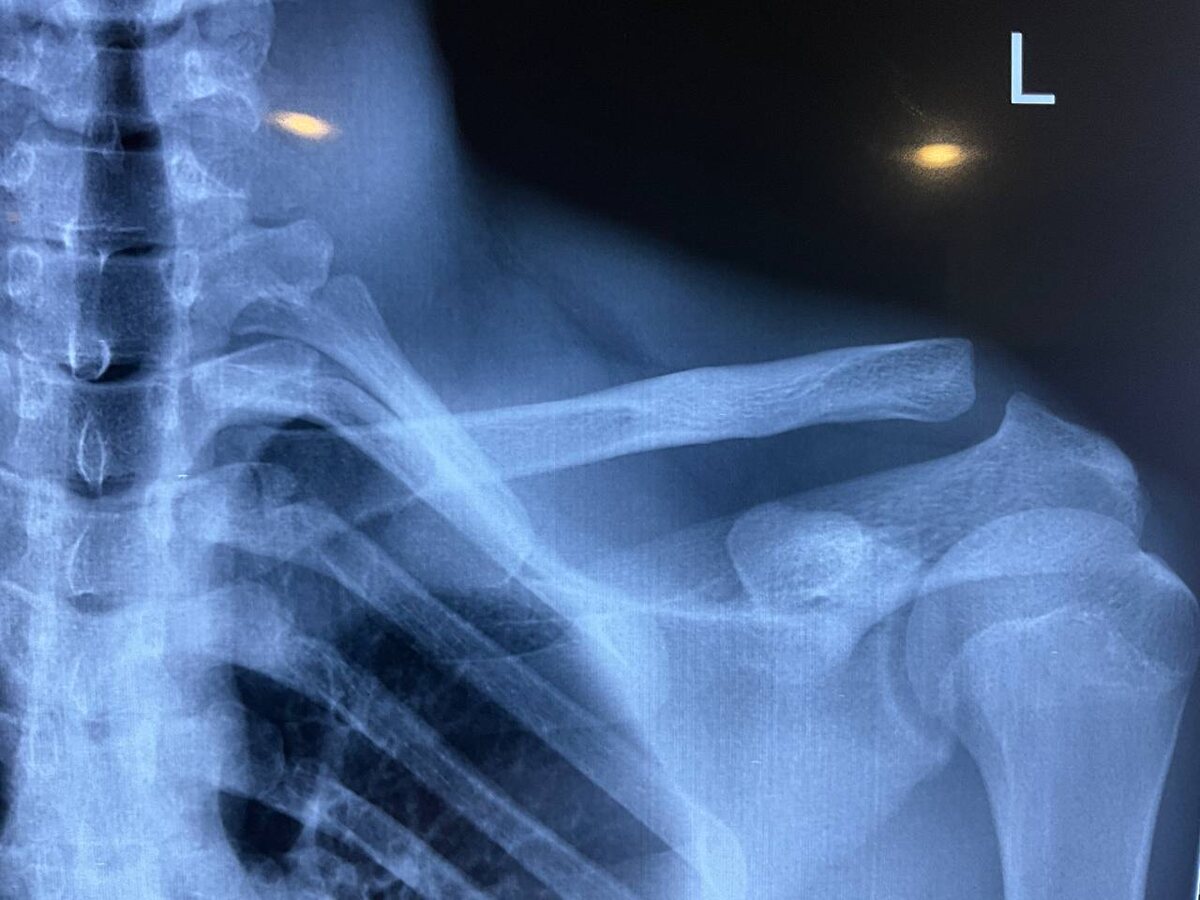

Травма плечевого пояса у спортсменов

Для спортсменов консервативное лечение (без операции) при полных вывихах ключицы (особенно акромиально-ключичного сочленения) сопряжено с рядом специфических рисков, которые могут критически повлиять на спортивную карьеру: Для профессиональных игроков и активных любителей при полных вывихах (III типа и выше) чаще рекомендуется оперативное вмешательство, чтобы восстановить анатомическую целостность и обеспечить стабильность плечевого пояса в условиях высоких нагрузок. Если вам требуется медицинская консультация или постановка диагноза, обратитесь к специалисту.

Для спортсменов консервативное лечение (без операции) при полных вывихах ключицы (особенно акромиально-ключичного сочленения) сопряжено с рядом специфических рисков, которые могут критически повлиять на спортивную карьеру:

Для профессиональных игроков и активных любителей при полных вывихах (III типа и выше) чаще рекомендуется оперативное вмешательство, чтобы восстановить анатомическую целостность и обеспечить стабильность плечевого пояса в условиях высоких нагрузок.